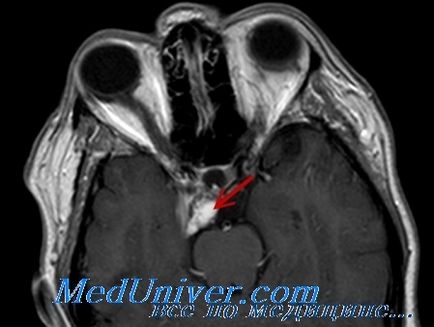

Tekintettel a rendkívül lassú növekedés glioma választott kezelést egyedileg kell meghatározni. Miközben a látás és képes a betegnél figyelni célszerű kijelölni a külső besugárzás. Sugárkezelés után jelölt stabilizációs a növekedését és fenntartását a látási funkció közel 75% -ánál. Sebészeti kezelés javallt korlátozásában tumornövekedés orbitális szegmense a látóideg és a hiánya a vizuális funkció.

Amikor kiválasztunk egy kezelést. akkor használja a következő szabály: ha van egy egyoldalú duzzanat az orbitális része a látóideg és a látás gyors romlása, sebészeti kezelés. A kérdés tartani a szemét megoldotta a műtét előtt. Ha a daganat átterjedt a szemfehérje gyűrű, ami miatt jól CT, látóideg károsodás kell távolítani együtt a szem, ami szükséges, hogy megakadályozzák a művelet egy beteg gyermek rokonai.

Vénás pangás retinopátia és a szemfenéki vagy jeleinek neovaszkuláris glaukóma kereslet valószínűleg koponyán hozzáférést, t. Hogy. Ezek a tünetek jelzik a terjedését a tumorból a csatorna a látóideg. De ilyen esetekben az a kérdés, sebészeti kezelés megoldja idegsebész.